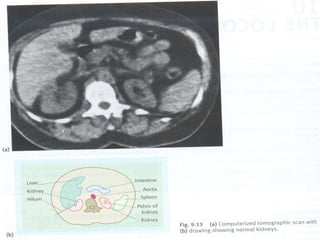

 TAC e MRI

Outros Analisis  Taxade Glomerular Filtracão  Microbiological Exam de Urina  Medidos Funcão Tubular Rines  Radiografia Simples  Ultrosonografia  Intravenos Urografia  Antegrade e Retrograde Urografia  Cistografia  Radionuclide Estudo  TAC e MRI  Arterorafia e Venografia